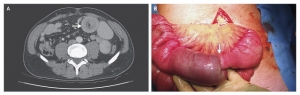

一例酷似结直肠癌的肠气囊肿

肠气囊肿(Pneumatosis coli,PC)是一种少见临床情况,也称作肠壁积气、肠壁囊样积气症,指消化道肠壁的浆膜下层或粘膜下层有多个充满气体的囊肿形成,可以表现为无症状,或表现为腹痛、腹胀、腹泻便秘、粘液样便或 ...